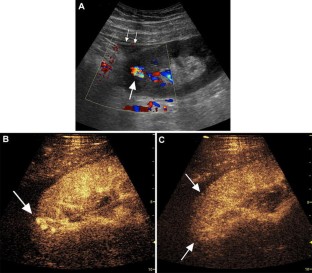

Fig. 3